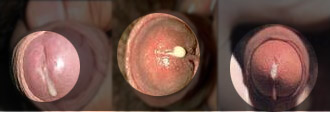

1、尿道炎:尿道炎以淋菌性和非淋菌性为主,临床症状主要是尿频、尿急、尿痛、尿不尽等。如果发现生殖器有黄色分泌物,并伴随上述症状,需要到医院检查是否患上了尿道炎。

2、龟头炎:龟头炎是男子生殖器官因细菌侵入组织引起局部红、肿、热、痛的一种化脓性疾病。在临床上可以分为急性前表性龟头炎、环状溃烂性龟头炎、念珠菌性龟头炎和滴虫性龟头炎四种。